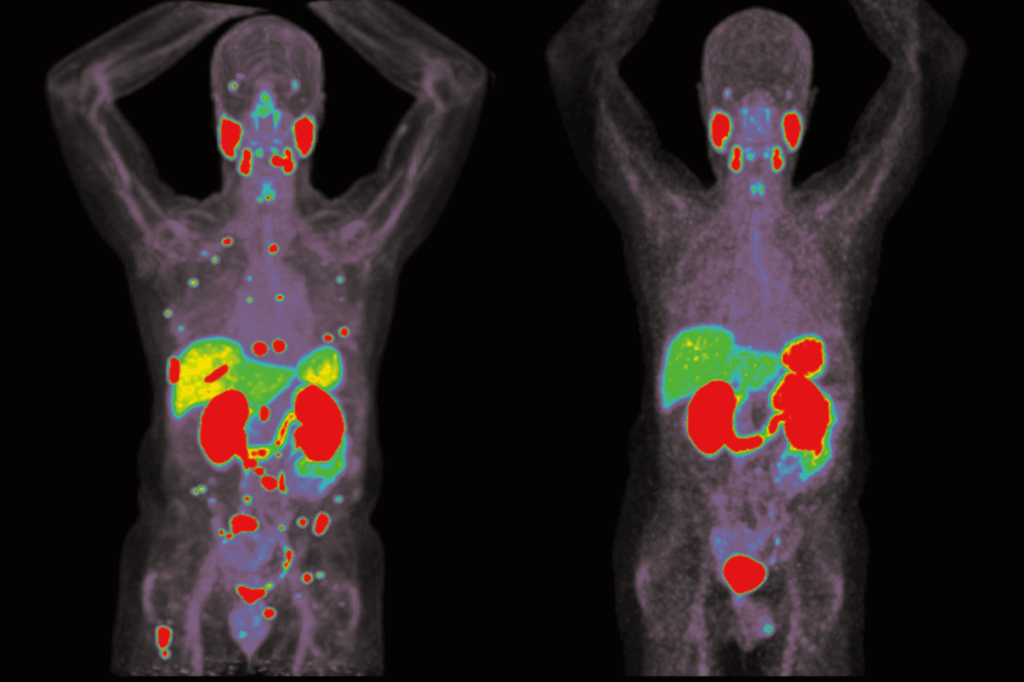

在 UCLA Health 的治疗下,Anisa 的病情改善显著。经过仅 5 个月的 Selpercatinib 治疗,她肺部结节明显缩小;血清甲状腺球蛋白(Thyroglobulin)水平从 23 ng/mL 降至不到 0.8 ng/mL(不到一年)。

更重要的是,她在治疗过程中未出现严重副作用,能够保持积极的生活状态,并重返足球赛场。这一成功案例表明,这种“先靶向、后放疗”的反向治疗策略,可能成为 RET 驱动型甲状腺癌 患儿的新标准方案。